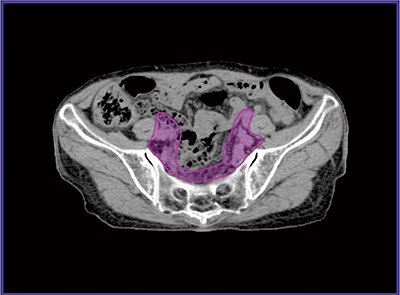

●標的体積

子宮癌に対する全骨盤照射では,かつては骨構造をランドマークとして照射野を決定する,二次元的な放射線治療計画が行われていた。三次元治療計画が一般化した現在,当院でも臨床的標的体積(CTV)を治療計画装置上で描画し(図1),これに適切なマージンを付与したものを計画標的体積(PTV)としている。子宮頸癌の臨床的標的体積については,国内外からガイドラインが発表されており1)〜3),当院もこれらのガイドラインを参考に標的体積を決定している。

図1 子宮頸癌に対する全骨盤照射における臨床的標的体積描画例